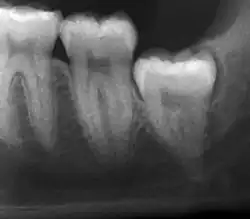

Radiograph of symptomatic and infected impacted wisdom tooth near inferior alveolar nerve